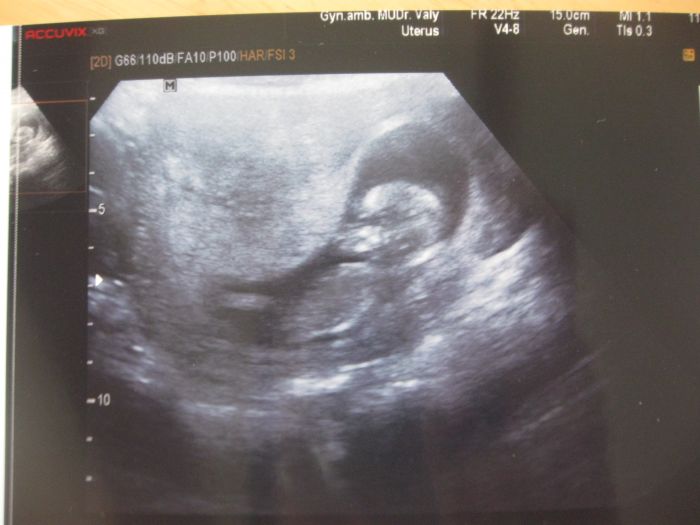

Teď jsem nějaký 15tt a 1.4. mě čeká další kontrola a nějaké krevní testy, krom jednoho šíleného krvácení ve 13tt, kdy jsem myslela, že je vše ztraceno a čekali mě 3 dny v nemocnici, je všechno v pořádku, akorát neustále špiním, by mělo být všechno v pořádku :) ... Tak doufám, že mimi opravdu donosím, o čem samozřejmě nepochybuji a k našemu adoptovanému Adámkovi se nám podaří ještě Evička :) (pohlaví zatím nevím)

Připojím i naše první foto